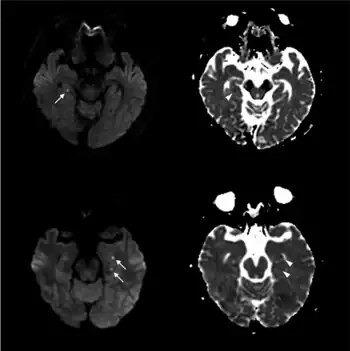

| Abnormal hippocampus findings consistent with transient global amnesia on MRI | |

.png.webp)

Unless there are concerning features, limited testing is required.[1] Medical imaging and lumbar puncture are generally not required.[1]

Recently, moreover, both imaging and neurocognitive testing studies question whether TGA is as benign as has been thought. MRI scans of the brain in one study showed that among people who had experienced TGA, all had cavities in the hippocampus, and these cavities were far more numerous, larger, and more suggestive of pathological damage than in either healthy controls or a large control group of people with tumor or stroke.[15] Verbal and cognitive impairments have been observed days after TGA attacks, of such severity that the researchers estimated the effects would be unlikely to resolve within a short time frame.[16] A large neurocognitive study of patients more than a year after their attack has shown persistent effects consistent with amnestic mild cognitive impairment (MCI-a) in a third of the people who had experienced TGA.[37] In another study, "selective cognitive dysfunctions after the clinical recovery" were observed, suggesting a prefrontal impairment.[13] These dysfunctions may not be in memory per se but in retrieval, in which speed of access is part of the problem among people who have had TGA and experience ongoing memory problems.[12]